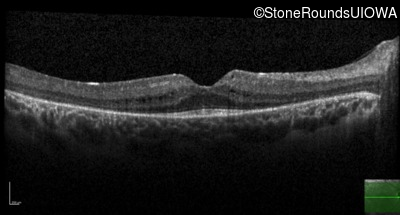

Age at visit: 7 years

OD OS

Age at visit: 10 years